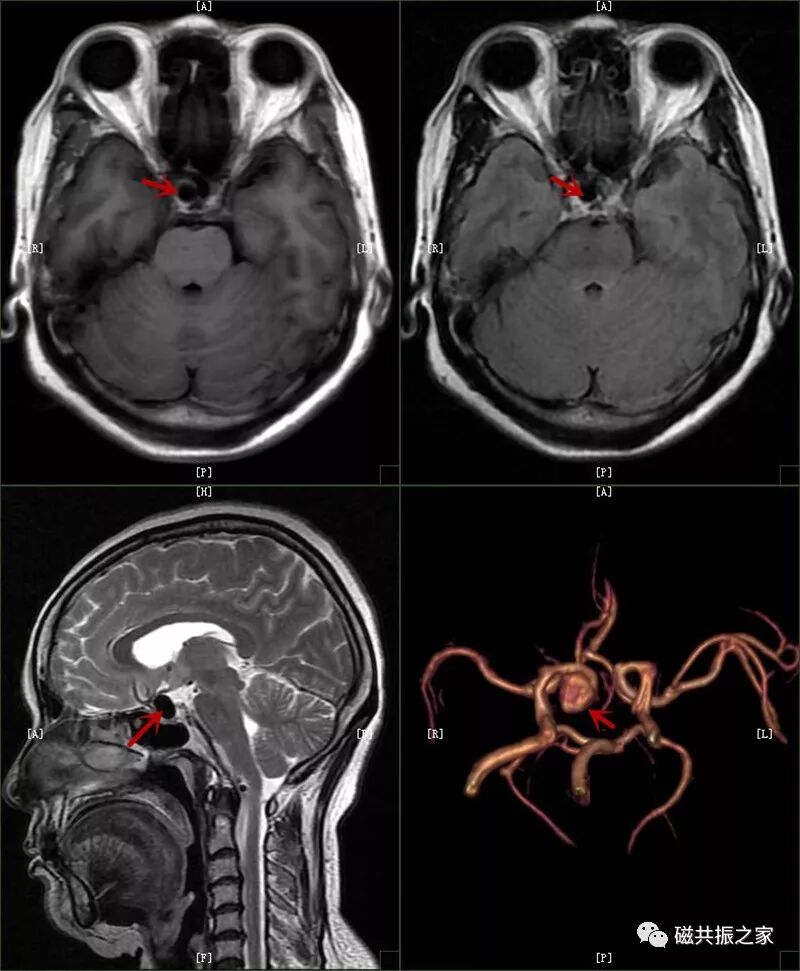

2.中枢神经系统:脑内(脑干)出血,出血量大于 30ml;蛛网膜下腔出血急性期;大范围脑挫裂伤;急性大面积脑梗死,颅内大动脉瘤,动脉瘤破裂。

图片D:-CT-MR室资料新闻稿文件夹微信图片_20211127090817.jpg颅内动脉瘤

D:-CT-MR室资料新闻稿文件夹微信图片_20211127090821.jpg颅内动脉瘤并出血